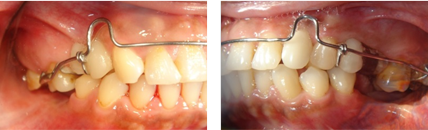

後續矯正以建立出已喪失的空間